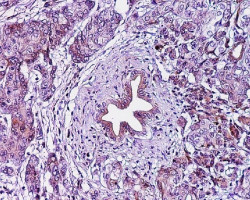

La cirugía es un tratamiento viable para los pacientes con cáncer de páncreas, especialmente tras la quimioterapia

Los pacientes con cáncer de páncreas en estadio II que reciben quimioterapia seguida de una intervención para eliminar la parte cancerosa del órgano, viven casi el doble de tiempo que los pacientes que reciben quimioterapia sola, según una nueva investigación publicada en línea en el `Journal of the American College of Surgeons`.